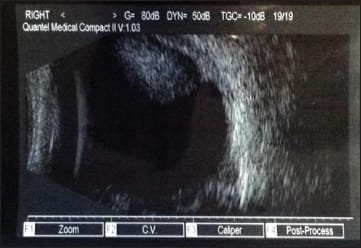

A dilated fundus exam of the right eye was significant for a clear vitreous. There was a normal optic nerve with a 0.3 cup-to-disc ratio. The macula and peripheral retinal exam were significant for extensive subretinal and choroidal hemorrhages in the superior and nasal periphery. B-scan ultrasonography confirmed the presence of the subretinal/choroidal hemorrhages (Figure 1). No subretinal or choroidal lesions were noted. The dilated fundus exam of the left eye was unremarkable.

Figure 1. B-scan ultrasonography confirmed the presence of subretinal/choroidal hemorrhages in this 21-year-old man with sudden vision loss.